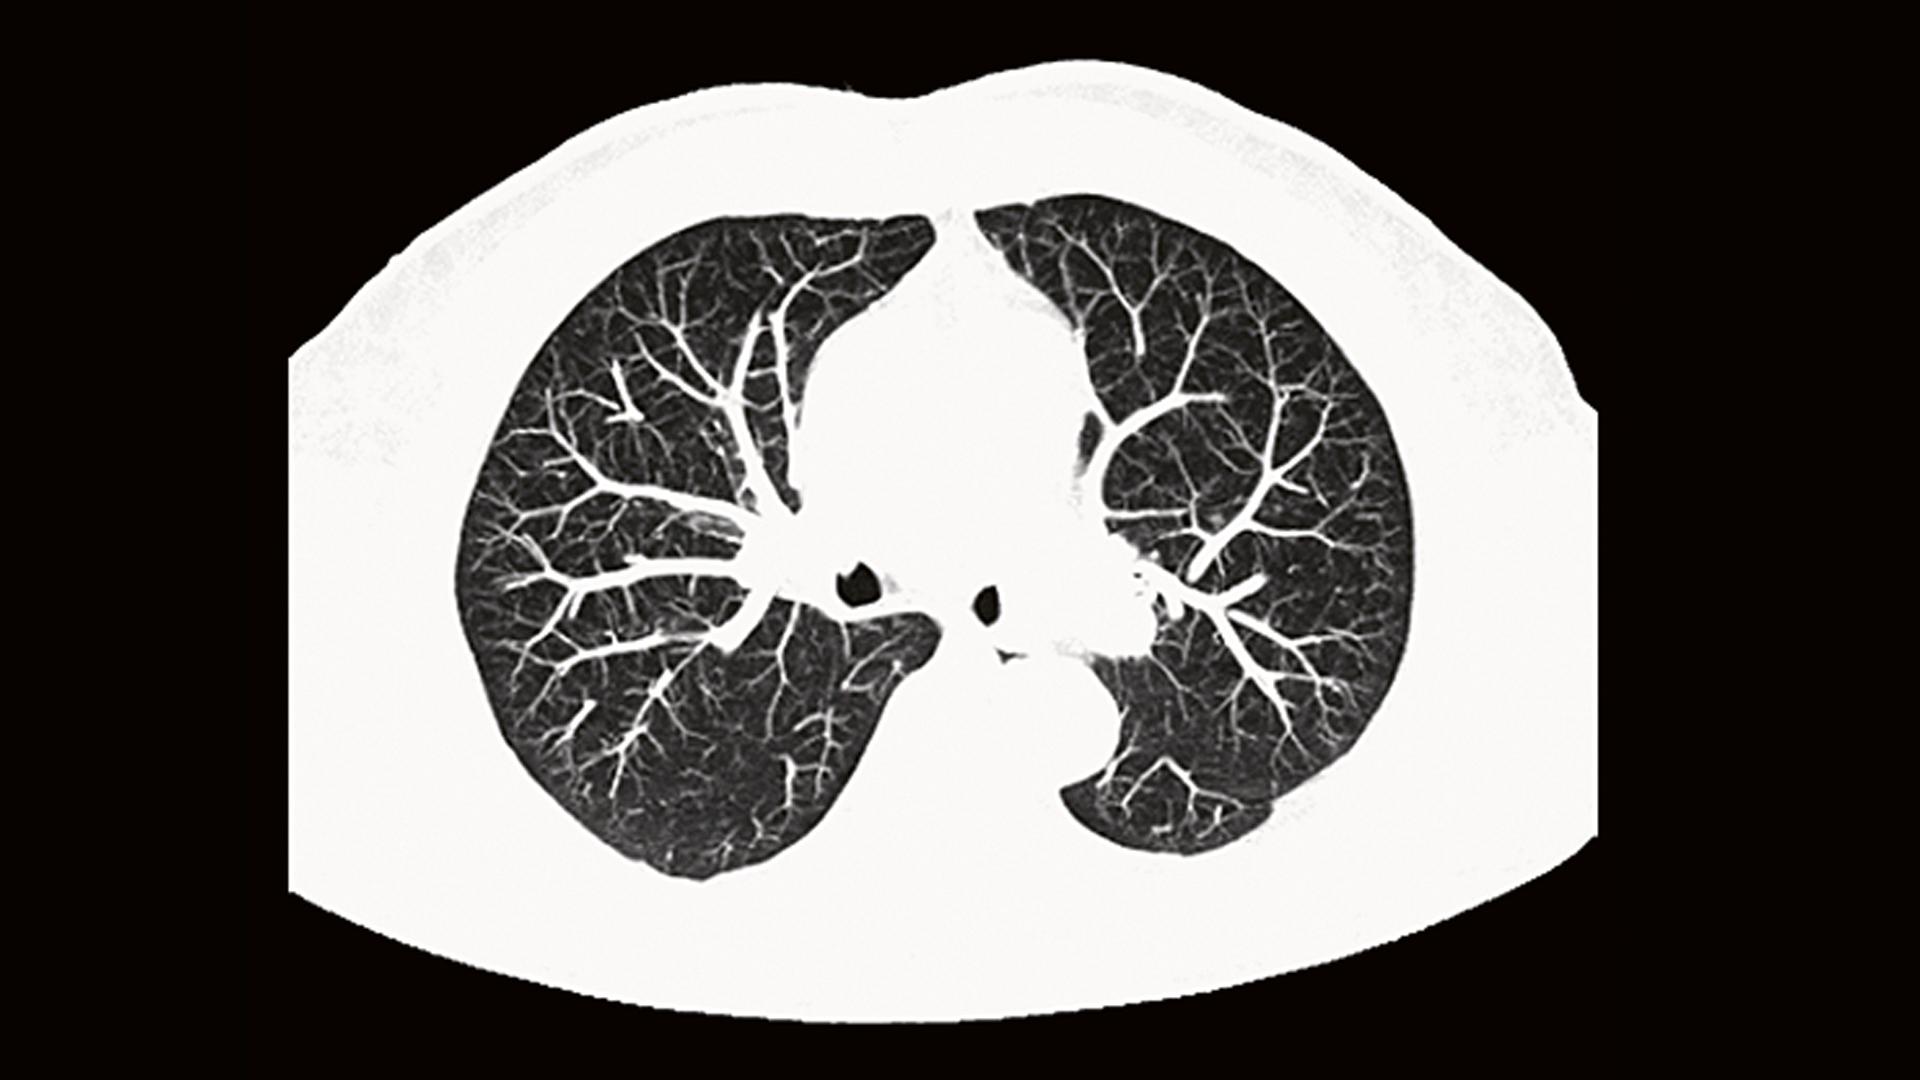

Кт легких детям

Кт легких детям 105 фотографий